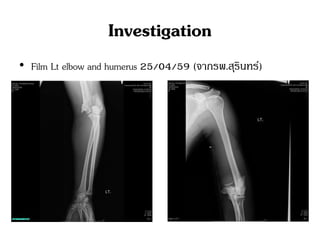

Investigation

• Film Lt elbow and humerus 25/04/59 (จากรพ.สุรินทร์)